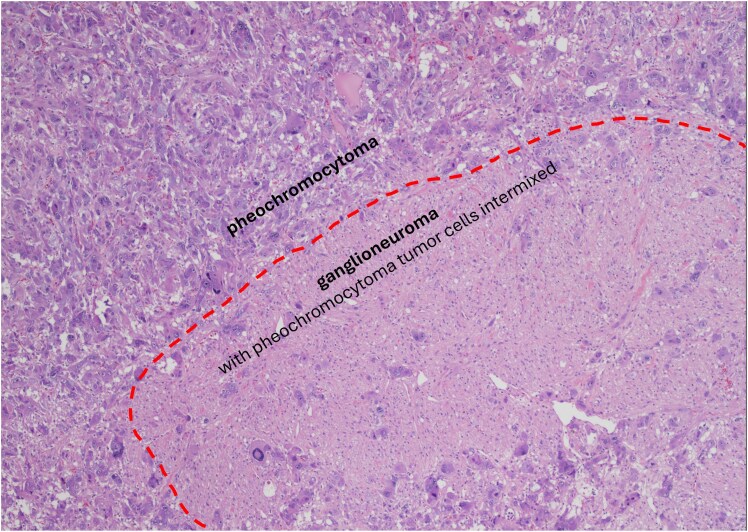

Context: Cells derived from neural crest populate several organs. A particular precursor cell, sympathogonia, gives rise to pheochromoblasts and neuroblasts. Due to common origin, tumors originating from pheochromoblasts, such as pheochromocytoma (PHEO) and paraganglioma (PGL), may rarely coexist with ganglioneuroma (GN).

Results: We identified 19 consecutive patients with PPGL-GN and 86 patients with PHEO. Patients with PPGL-GN, compared to those with PHEO, were younger (aged 46.0 vs 50.8 years; P = .03), had higher rate of underlying genetic disorders (47.4% vs 23.2%; P = .03), and had fewer functioning tumors (89.5% vs 100%; P = .002). There was no difference in the median radiological tumor size or the precontrast computed tomography density. Disease recurrence (at another site) was noted in 15.8% of PPGL-GN patients who had a median follow up of 14.6 months, as opposed to no disease recurrence in patients with PHEO. There was no documented recurrence at the tumor bed and no metastasis in both groups.

Conclusion: Patients with PPGL-GN were younger and had a higher occurrence of underlying genetic disorders compared to PHEO. However, PPGL-GN was radiologically indistinguishable from PHEO. The higher observed disease recurrence of PPGL-GN reinforces vigilant postoperative follow-up.